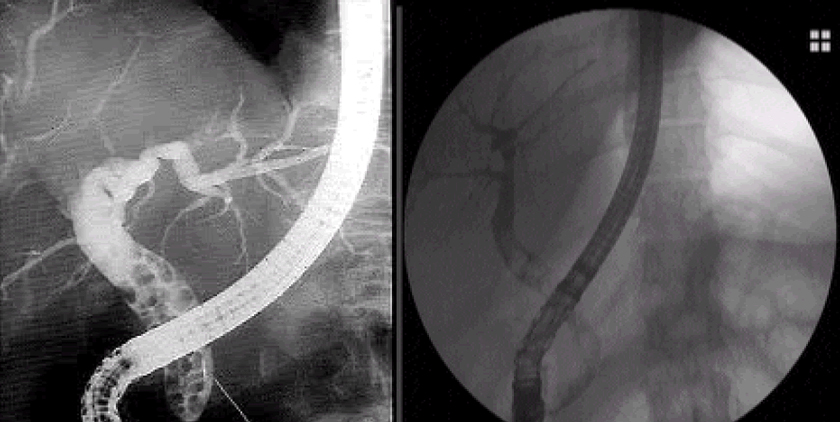

Endoskopik Ultrason ve ERCP: Endoskopik retrograd kolanjiyopankreatografi veya ERCP, safra kesesi, pankreas ve safra kanallarını incelemek için kullanılan özel bir endoscopik tekniktir ve tedavi edici bir araç olmanın yararına sahiptir. ERCP 30 yılı aşkın bir süredir kullanılmaktadır ve safra yollarının bozukluklarının teşhisi ve tedavisi için standart yöntem olarak kabul edilmektedir. ERCP sırasında, hastalar önce hafif bir yatıştırıcı ile birlikte boğazı uyuşturmak için bir anestezi alırlar. Gastroenteroloğunuz daha sonra ağzınızın içinden ve mideye ve ince bağırsağa bir minyatür TV kamerasıyla esnek bir endoskop geçirecektir. Gastroenteroloğunuz bir monitörde safra ve pankreas kanallarını gördüğünde, ERCP aracılığıyla ince bir ultrason probu geçirir. Endoscopic ultrason (EUS) safra ve pankreatik kanalların daha iyi görüntülenmesi için X ışınları yerine ultrason görüntüleri kullanır. Bu endoscopik işlem için özel hazırlıklar gereklidir.